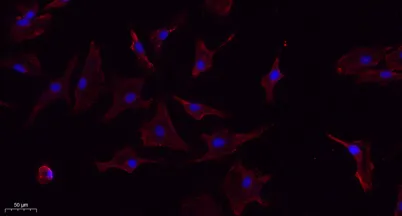

- Validated Applications: WB, IHC, IF, ELISA

- Dilution: Western Blot: 1/500 - 1/2000. IHC-p: 1:100-300 ELISA: 1/20000. IF 1:100-300 Not yet tested in other applications.